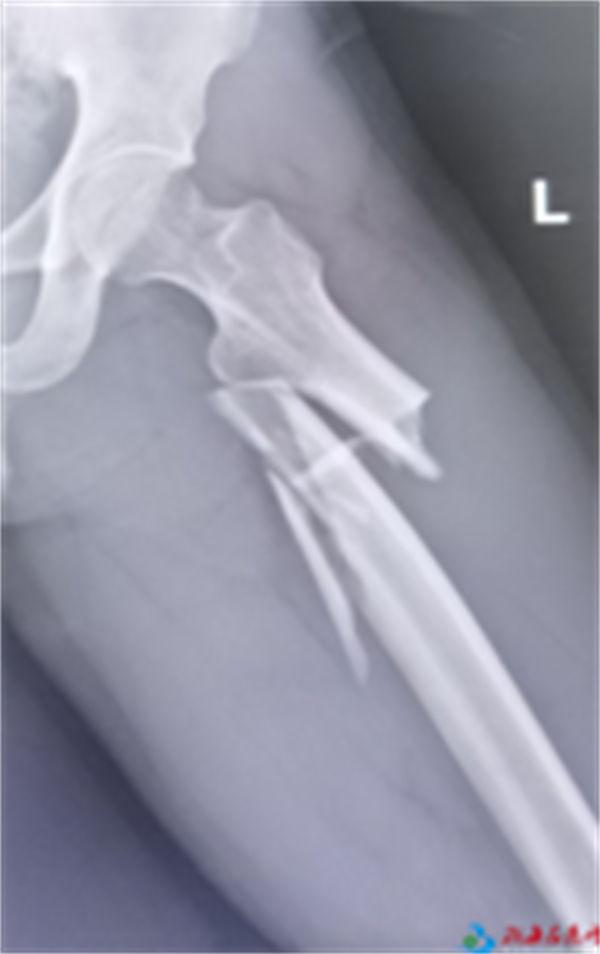

入院后,经过创伤中心副主任医师戴勇和团队成员主治医师吴培伟、孙麟、规培医生霍赛赛等初步检查,患者全身创伤多达14处——左侧股骨干近端粉碎性骨折;右侧髂骨及耻骨上支骨折;左侧髋臼骨折;右侧桡骨远端伴尺骨茎突骨折;右腕三角骨骨折;右腕月骨脱位;右腕部神经损伤;右第1指近节指骨远端骨折;左侧桡骨中段骨折;右肾包膜下出血;肝下缘及右侧结肠挫伤;头部损伤;鼻骨骨折(疑似);面部挫伤及右小腿挫伤。

左侧股骨骨折切开复位植骨髓内钉内固定术;